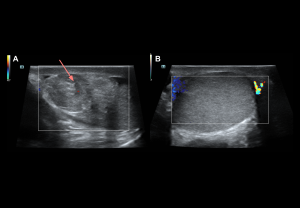

Grey-scale:

- Early (<6 h): normal echogenicity

- Acute (<6 h): testis enlargement, thickened scrotal coverings, reactive hydrocele, altered epididymal echogenicity or position.

- Late: reduced size, heterogeneous echotexture; hypoechoic areas

Doppler findings:

- Degree of torsion:

- Complete (≥360°): Usually absent intratesticular flow.

- Partial (<360°): Residual intratesticular flow may be detectable.

- Spectral Doppler: Increased resistive index (RI) and possible diastolic flow reversal, whirlpool sign of spermatic cord

- Late (>24 h): Periscrotal hyperaemia reflects inflammation.